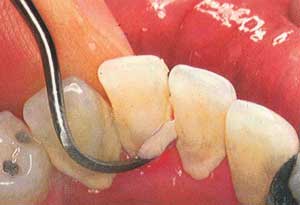

avenjers71 (7) گزارش تخلف عوامل موضعی مؤثر در بیماریهای لثه یكی از عوامل التهاب باكتریهای موجود در پلاك است. جرمها، كارهای غلط دندانپزشكی و پروتزهای ثابت و متحرك و خرده غذایی كه قبلا وجود داشتهاند، نیز از عوامل مسبب بیماریهای لثه است كه موجب ایجاد شرایط مساعد برای جمع شدن پلاك میگردد.تأثیر اصلی در این است كه روی سطح ناصاف آنها پلاكهای میكربی تجمع پیدا میكنند و این امر نقش مهمی در پیشرف... 9 0 0 57 5 سال پیش